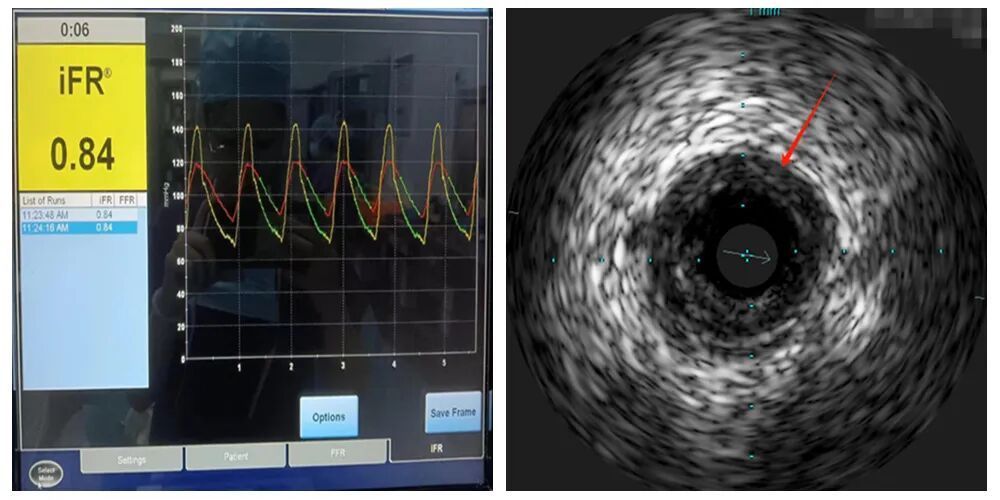

▲开展内地首例冠脉功能+影像一站式检查新技术

心血管内科在全方位迅速发展,为本区域人民群众提供优质心血管疾病诊治服务,且在服务质量、技术水平上持续改进。其中,在冠心病亚专科方面,医院及科室目前是中国国家胸痛中心,承担本区域急性心肌梗死等胸痛疾病患者的诊治任务。心血管专科连续三年冠状动脉介入治疗手术超过1200例/年(2025年突破1400例/年),冠脉造影量超过3000例/年,复杂高危病变介入手术技术不断突破(2024年开展内地首例冠脉功能+影像一站式检查技术),手术总量及手术成功率均位居粤东北地区首位,极大提升了为罹患疾病老百姓的服务能力。